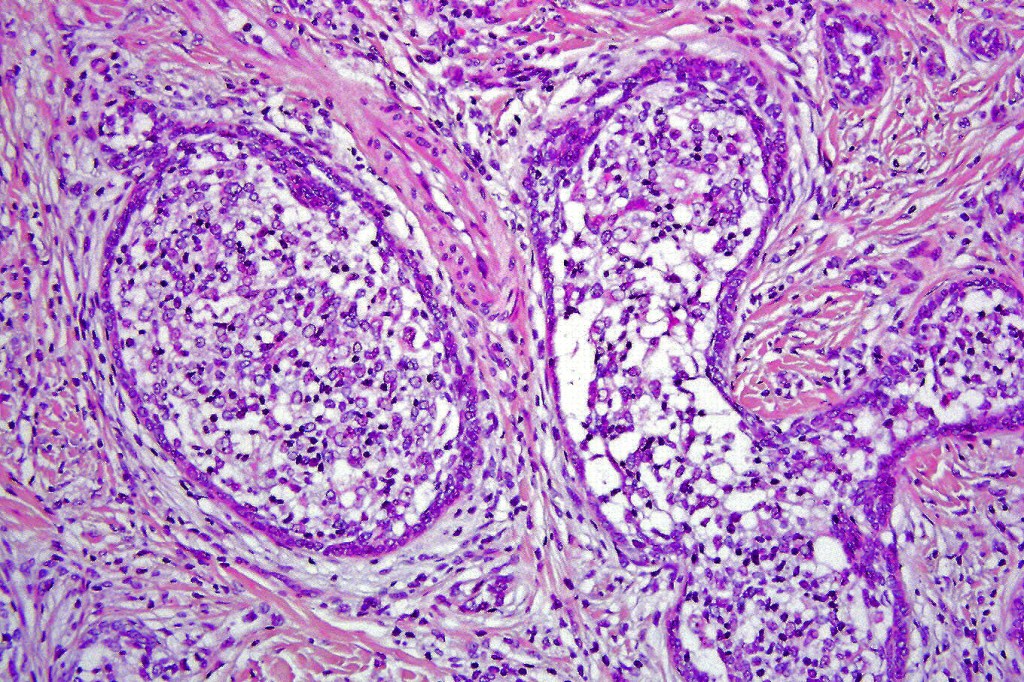

•Dermal nodule, rarely extends into subcutaneous fat

•Irregular lobules of epithelial cells embedded in a dense fibrous stroma

•Peripheral rim of darkly staining basaloid cells surrounding larger pale staining cells with vesicular nuclei with often prominent eosinophilic nucleoli

•Central cells PAS positive (glycogen)

•No pleomorphism or mitotic activity

•No retraction artifact or stromal mucin

•Admixed lymphocytes (an obligatory feature)

•Germinal centers sometimes present